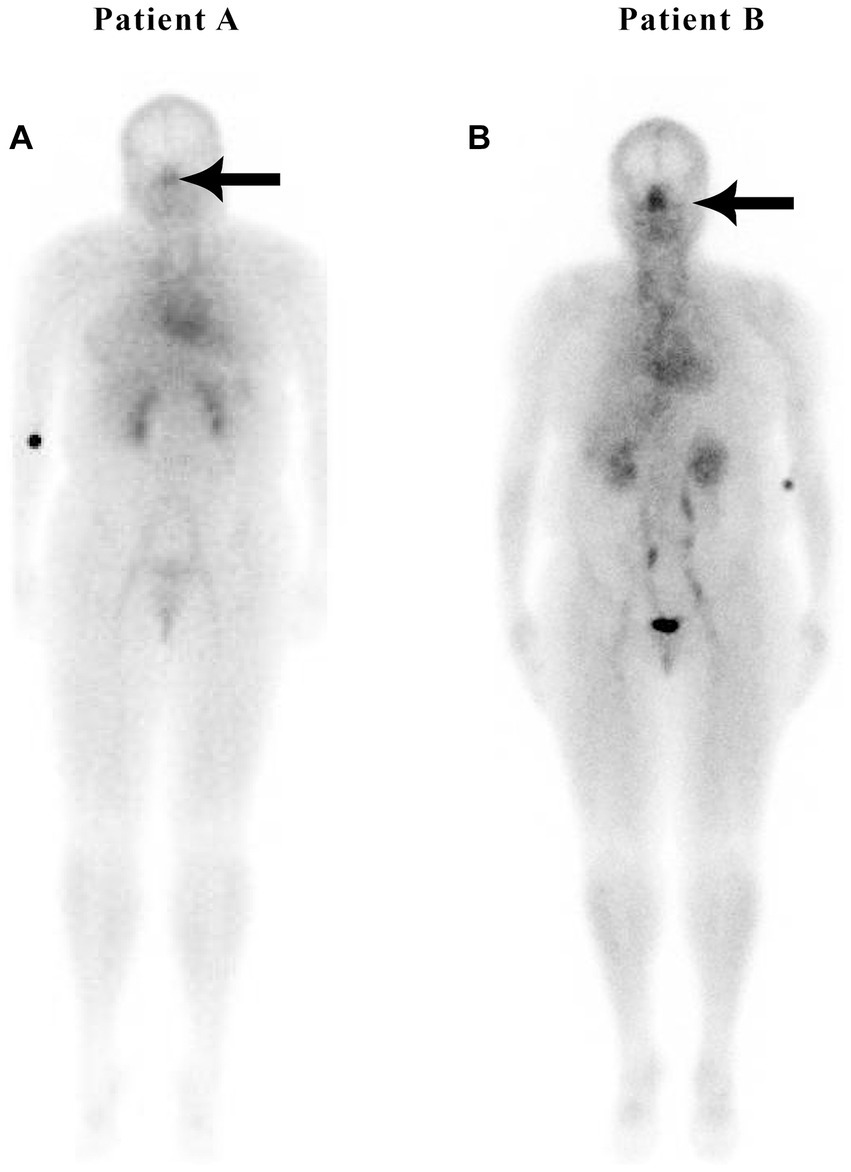

Figure 2 illustrates the nuclear medicine scan of weight-matched patients, both with an elevated body mass index (BMI). Patient A is a normal control and Patient B has hypertension and hyperlipidemia, but not diabetes or sleep apnea. There is increased nasal blood pooling in the overweight hypertensive patient compared to the overweight non-hypertensive control subject.

Figure 2

Weight-matched, non-hypertensive (A) vs. hypertensive patient (B), both with elevated BMIs.

Both non-hypertensive patients in Figures 1, 2 have very minimal blood activity in their nasal turbinates while both patients with hypertension have very significant activity in the nasal turbinate region. These whole-body blood pool imaging studies have provided insights to the investigators which have led to their proposal of a working hypothesis described in this paper regarding a new causation paradigm for essential hypertension. Confirmation of these findings will be important. Potential methods to confirm these findings will be addressed in section 19.

The authors recently published an article that described subjects with metabolic syndrome, including hypertension, increased BMI, diabetes, and sleep apnea, exhibiting significantly increased nasal blood volume (2–3-fold greater), also referred to as blood pooling, as compared with subjects without metabolic syndrome as determined by whole-body nuclear imaging (25). This unique phenomenon of nasal pooling has been observed by the author using scintigraphic whole-body imaging in patients with metabolic syndrome, regardless of their body habitus (Figure 3).

Figure 3

Nuclear medicine scans of patients with metabolic syndrome.

Figure 3 shows increased nasal blood pooling in both patients with metabolic syndrome, including essential hypertension. Patient A, a 59-year-old female with a BMI of 32.5, has less severe metabolic syndrome. She has hypertension and hyperlipidemia with high triglycerides and is being treated with 1 anti-hypertensive and 1 anti-hyperlipidemic medication. Patient B has more severe metabolic syndrome with a BMI of 43.3. The patient is a 55-year-old female with hypertension, diabetes, sleep apnea, and hyperlipidemia, and is being treated with 3 anti-hypertensive, 1 anti-hyperlipidemic, and 1 anti-hyperglycemic medication.

As in patients with hypertension and without complete metabolic syndrome, we hypothesize that those patients with metabolic syndrome have an increase in blood volume in their nasal region significantly decreasing the normal lymphatic transport or drainage through the nasal turbinates resulting in increased intracranial pressure. The increased intracranial pressure causes the increased systemic blood pressure as part of Cushing’s mechanism, i.e., the selfish brain’s attempt to maintain cerebral blood flow. Patient A, the patient on the left in Figure 3, has a less severe form of metabolic syndrome (without diabetes). She, however, has three of the five criteria of metabolic syndrome, including triglycerides over 150, a high waist circumference, and high blood pressure. Nonetheless, she has a high nose/heart ratio.